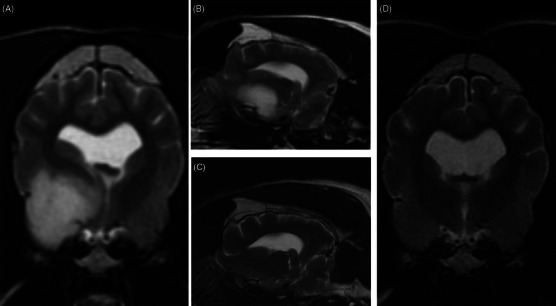

A 10-year-old female spayed boxer was treated with stereotactic radiotherapy (SRT) for a suspected glioma in the left piriform lobe. The intra-axial lesion was T2 hyperintense, T2 FLAIR hyperintense, T1 hypointense, and did not uptake contrast. Imaging was performed with an MRI every 3 months, and at the 6-month recheck, new lesions in the left hippocampus and right piriform lobe were evident without clinically apparent neurological progression. A second course of SRT was prescribed for the new lesions. Euthanasia was elected 14 months after the first course of SRT, and necropsy confirmed oligodendroglioma with drop metastasis.

Abstract Image